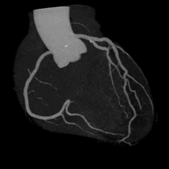

CTO、側副血行路例